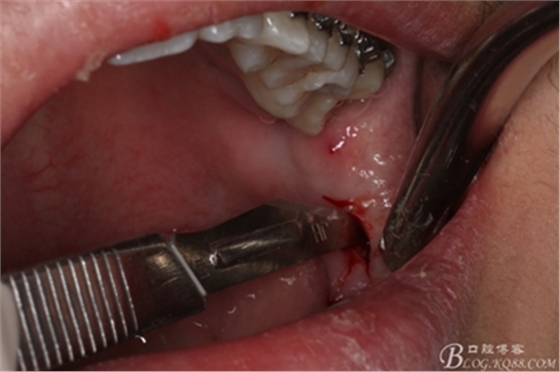

圖4.局部下牙槽神經(jīng)無痛阻滯麻醉